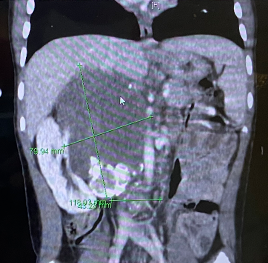

지호의 배 속에서 17cm 크기의 암이 발견되었고,

지호의 CT 사진 지호의 진단서 사진

수차례 항암에도 남아 있는 7cm 종양

지호의 배 속에는 여전히

7cm 크기의 종양이 남아 있습니다.